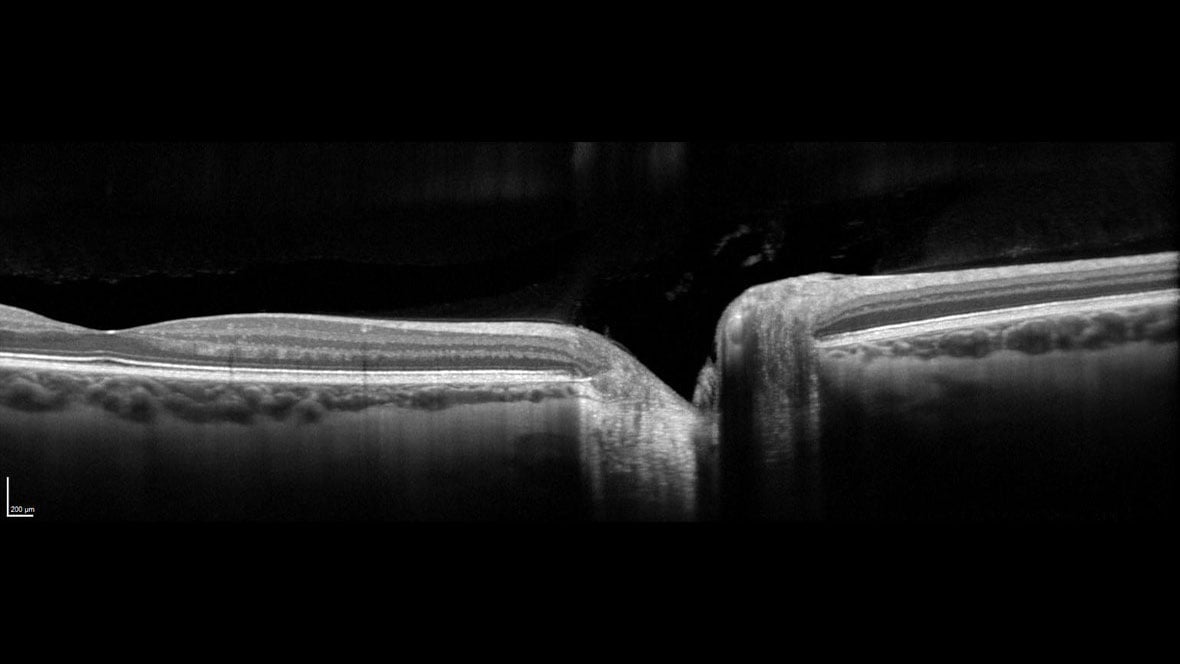

The SPECTRALIS SHIFT technology enables adaptation to the unique needs of the patient and clinic workflow by offering changeable OCT scan speeds. Use 20 kHz for maximum detail in eyes that are challenging to image, 85 kHz for optimal balance of speed and image quality, and 125 kHz for rapid scanning in time-sensitive or high-volume settings.